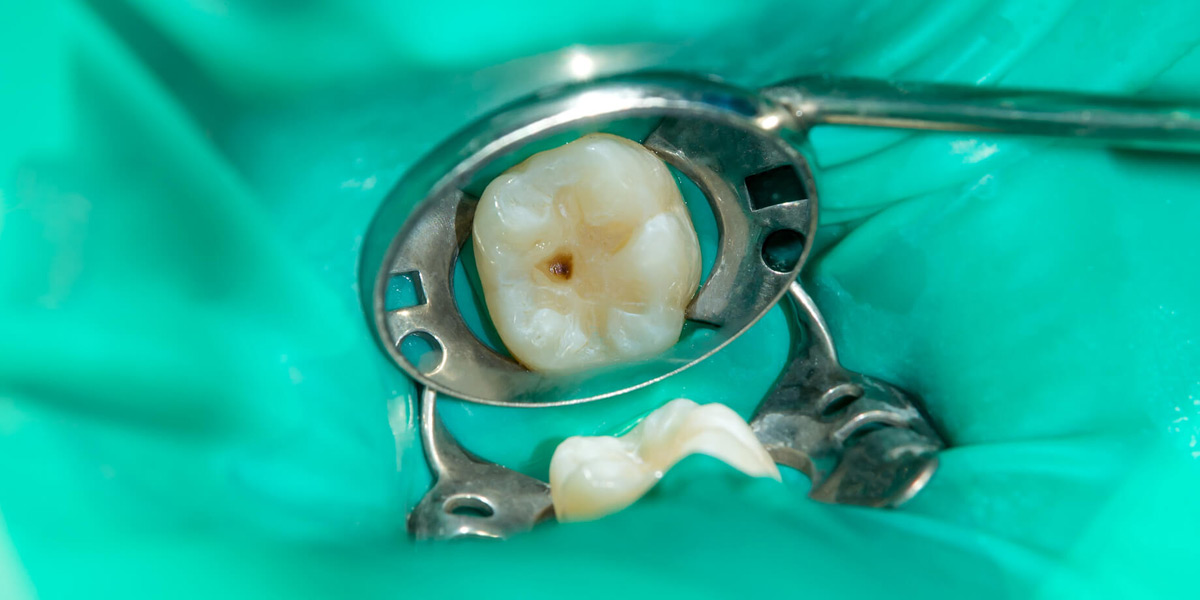

Разберем более подробно кариесрезистентность на органном уровне. Зуб как орган. Устойчивость или восприимчивость к этому заболеванию напрямую связана с количеством, величиной, глубиной ямок и фиссур зубов.

Типы фиссур

Фиссуры, имеющие постоянный диаметр на протяжении от устья до дна:

узкие (I-образные), состовляющие около 19% всех фисур

широкие (U-образные), на долю которых приходится 14% всех фиссур

Фиссуры с широким устьем и узким основанием, так называемые открытые фиссуры:

конусообразные (воронкообразные, V-образные, «острый угол»), составляющие 34% всех фиссур

фиссуры в форме полусферы (40%)

Фиссуры с узким устьем и широким, иногда разветвленным пространством в основании, так называемые закрытые фиссуры:

каплевидные, мешковидные, полипообразные, «обратный Y», «колба с узким горлом», составляющие около 26% всех фиссур.

Конечно же, более высокий риск возникновения кариеса будет у тех пациентов, зубы которых генетически имеют фиссуры закрытого типа. В них скапливается налет, пища, бактерии, они сложно поддаются очистке и гигиене.